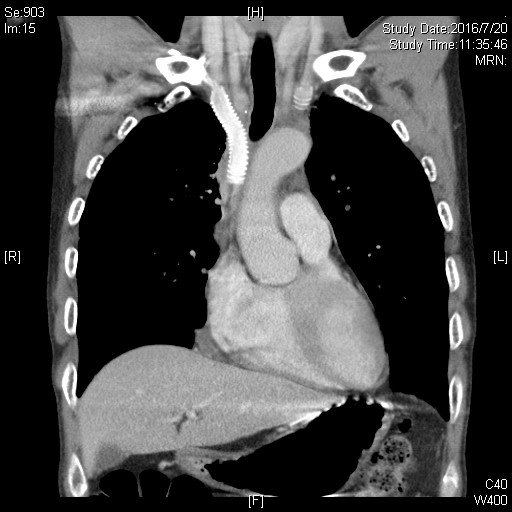

病例1——右肺上叶癌侵及肺门、左右无名及上腔静脉、右心房、心包及纵隔胸膜,行心包内右全肺、部分右心房、上腔静脉切除,人工血管原位置换术。

右肺上叶癌侵及心脏大血管分期为T4,常被认为无法切除,患者失去手术机会。既往不断有尝试切除并获得较好预后的报道,但手术难度大、围术期死亡率高仍是主要问题。此患者就诊前曾于外院行气管镜活检,病理提示肺腺癌。同时未见远处转移,具备手术指征。久经转诊的多家医院均认为无法手术。患者临床表现以上腔静脉阻塞综合征为主(头面部肿胀、静脉曲张、呼吸困难),成功切除肿瘤才能得到缓解。

手术采用胸骨正中切口,进胸后细致分离肿瘤与胸骨间粘连,充分探查后可见肿瘤侵及肺门、左右无名及上腔静脉、右心房、心包及纵隔胸膜。陈东红主任认为为达到R0切除,需进行右全肺、上腔静脉切除,人工血管重建。材料采用Gore-Tex带环人工血管,先以人工血管建立左无名静脉-右心耳血管桥,进一步心包内切除右全肺及受肿瘤侵犯的部分右心房,手工牢固缝合右心房,整块切除肿瘤后搭右无名静脉-右心耳血管桥。进一步彻底清扫纵隔淋巴结。完成手术后可见人工血管充盈,心脏搏动有力,血液动力学指标平稳。切除肿瘤标本直径约8cm,手术时间约7小时。